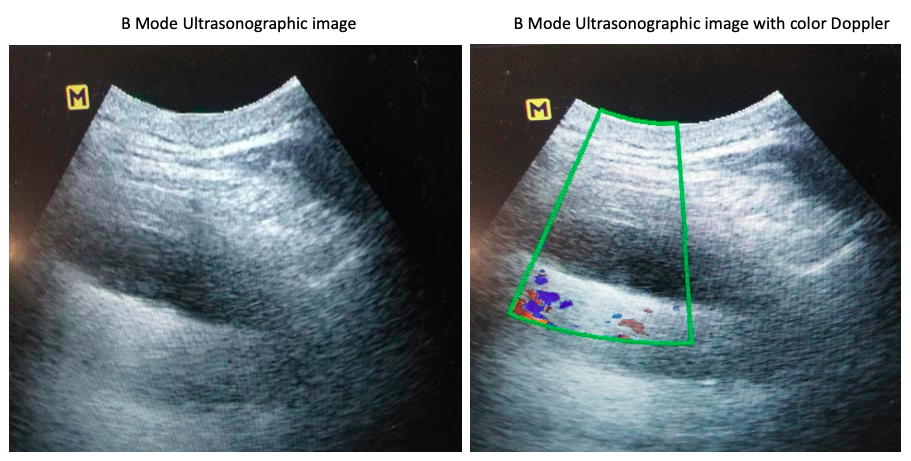

A 39-year-old, man presented to the chest clinic with complaints of right-sided chest pain and mild exertional dyspnea for the last six months. The pain was dull aching in nature and localized to the right lower axillary area and back. There was no history of fever, weight loss or loss of appetite. He had completed six months of anti-tubercular therapy (Rifampicin, isoniazid, ethambutol and pyrazinamide) on a clinical-radiological basis for right-sided pleural effusion one year back. On physical examination his heart rate was 84/min, respiratory rate was 16/min, saturation was 98% at room air by pulse oximetry and blood pressure 134/80 mm of Hg. The respiratory system examination revealed decreased vesicular breath sounds in the right infra-axillary and infra-scapular areas. All the routine blood investigations including haemogram, liver profile and renal profile were within normal limits. His chest radiograph showed blunting of the right costophrenic angle (figure 1). The B mode ultrasonographic image of the right lower chest wall alone and with the colour Doppler is shown in figure 2.

Name the ultrasonographic sign shown in figure 2. What is the diagnosis?

A. Presence of fluid colour sign, pleural effusion.

B. Absent fluid colour sign, pleural thickening.

C. Absent fluid colour sign, pleural effusion.

D. Presence of fluid colour sign, pleural thickening.